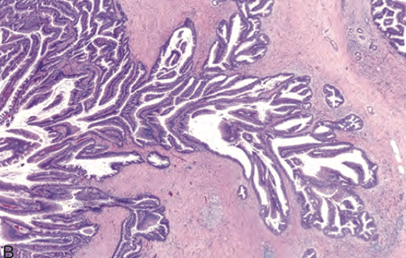

31세 여자가 등과 옆구리의 간헐적 통증으로 병원에 왔다. 복부 전산화 단층촬영(사진 A)에서 췌장 미부에 비교적 경계가 좋은 장경 3 cm 크기의 낭성 종양이 발견되어 절제술을 시행하였다. 사진(사진 B)은 이 종양의 조직학적 소견 및 β-catenin에 대한 면역조직화학 염색 결과이며, β-catenin 유전자 (CTNNB1)의 돌연변이가 관찰되었다. 진단은?

• 종양 내부에는 solid과 cystic한 부분이 함께 존재하며, cystic한 부분은 hemorrhagic debris로 가득 차 있다. 조직학적으로는 겹들을 형성하는 pseudopapillary한 구조들이 관찰되며, 잘 분리되지 않은 특징을 가진다.